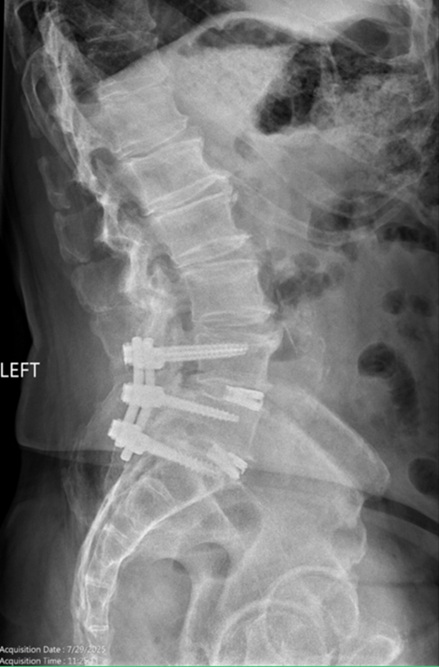

Figures 6 and 7. AP and Lateral of the Lumbar spine demonstrating previous lumbo-sacral fusion.

Pre-op Spine Images

Figure 5.

Figure 6.